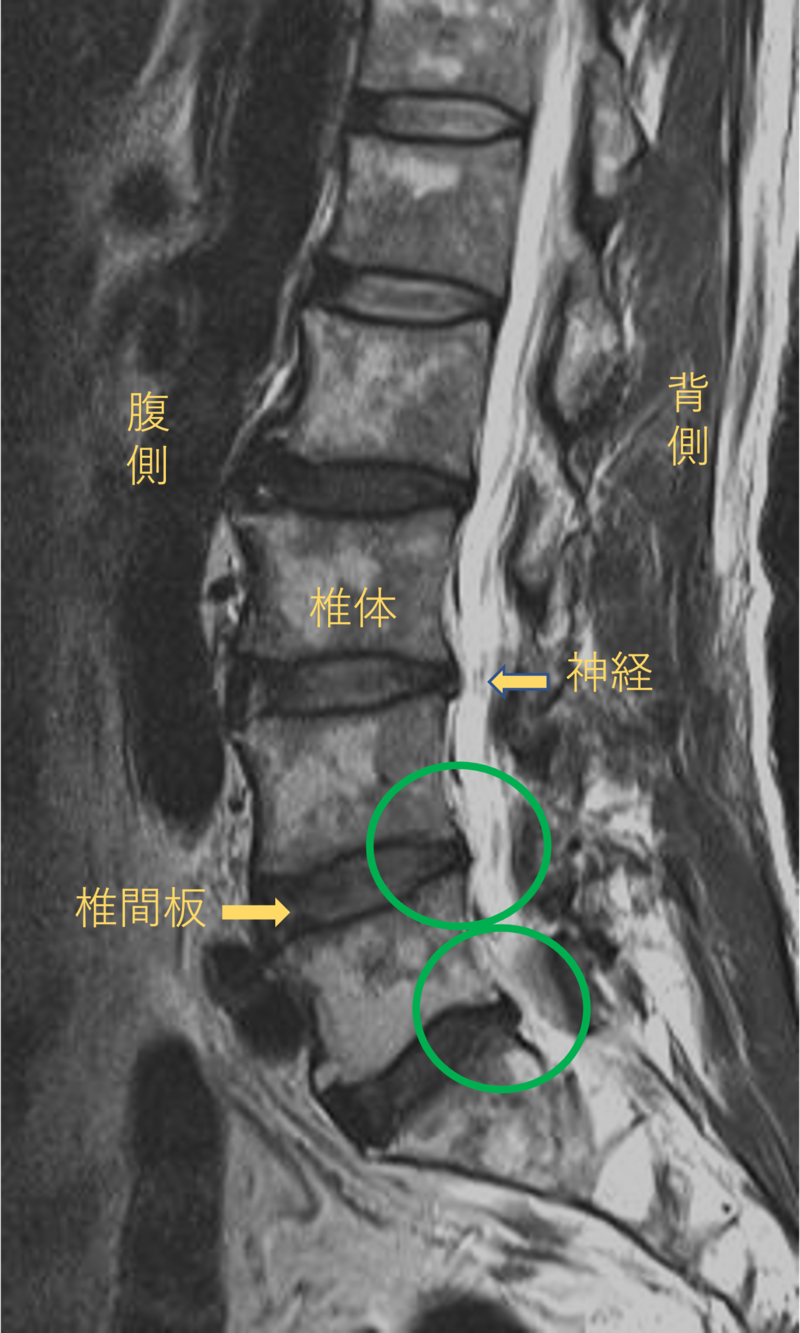

腰を横から見たMRI画像です。

腰椎という骨と骨の間に椎間板と呼ばれるクッションがあります。

このクッションの中身が飛び出す状態が椎間板ヘルニアと呼ばれます。

このMRI画像では、椎間板が背中側に飛び出して足に向かう神経が圧迫されることが痛み、しびれの原因となっておりました。